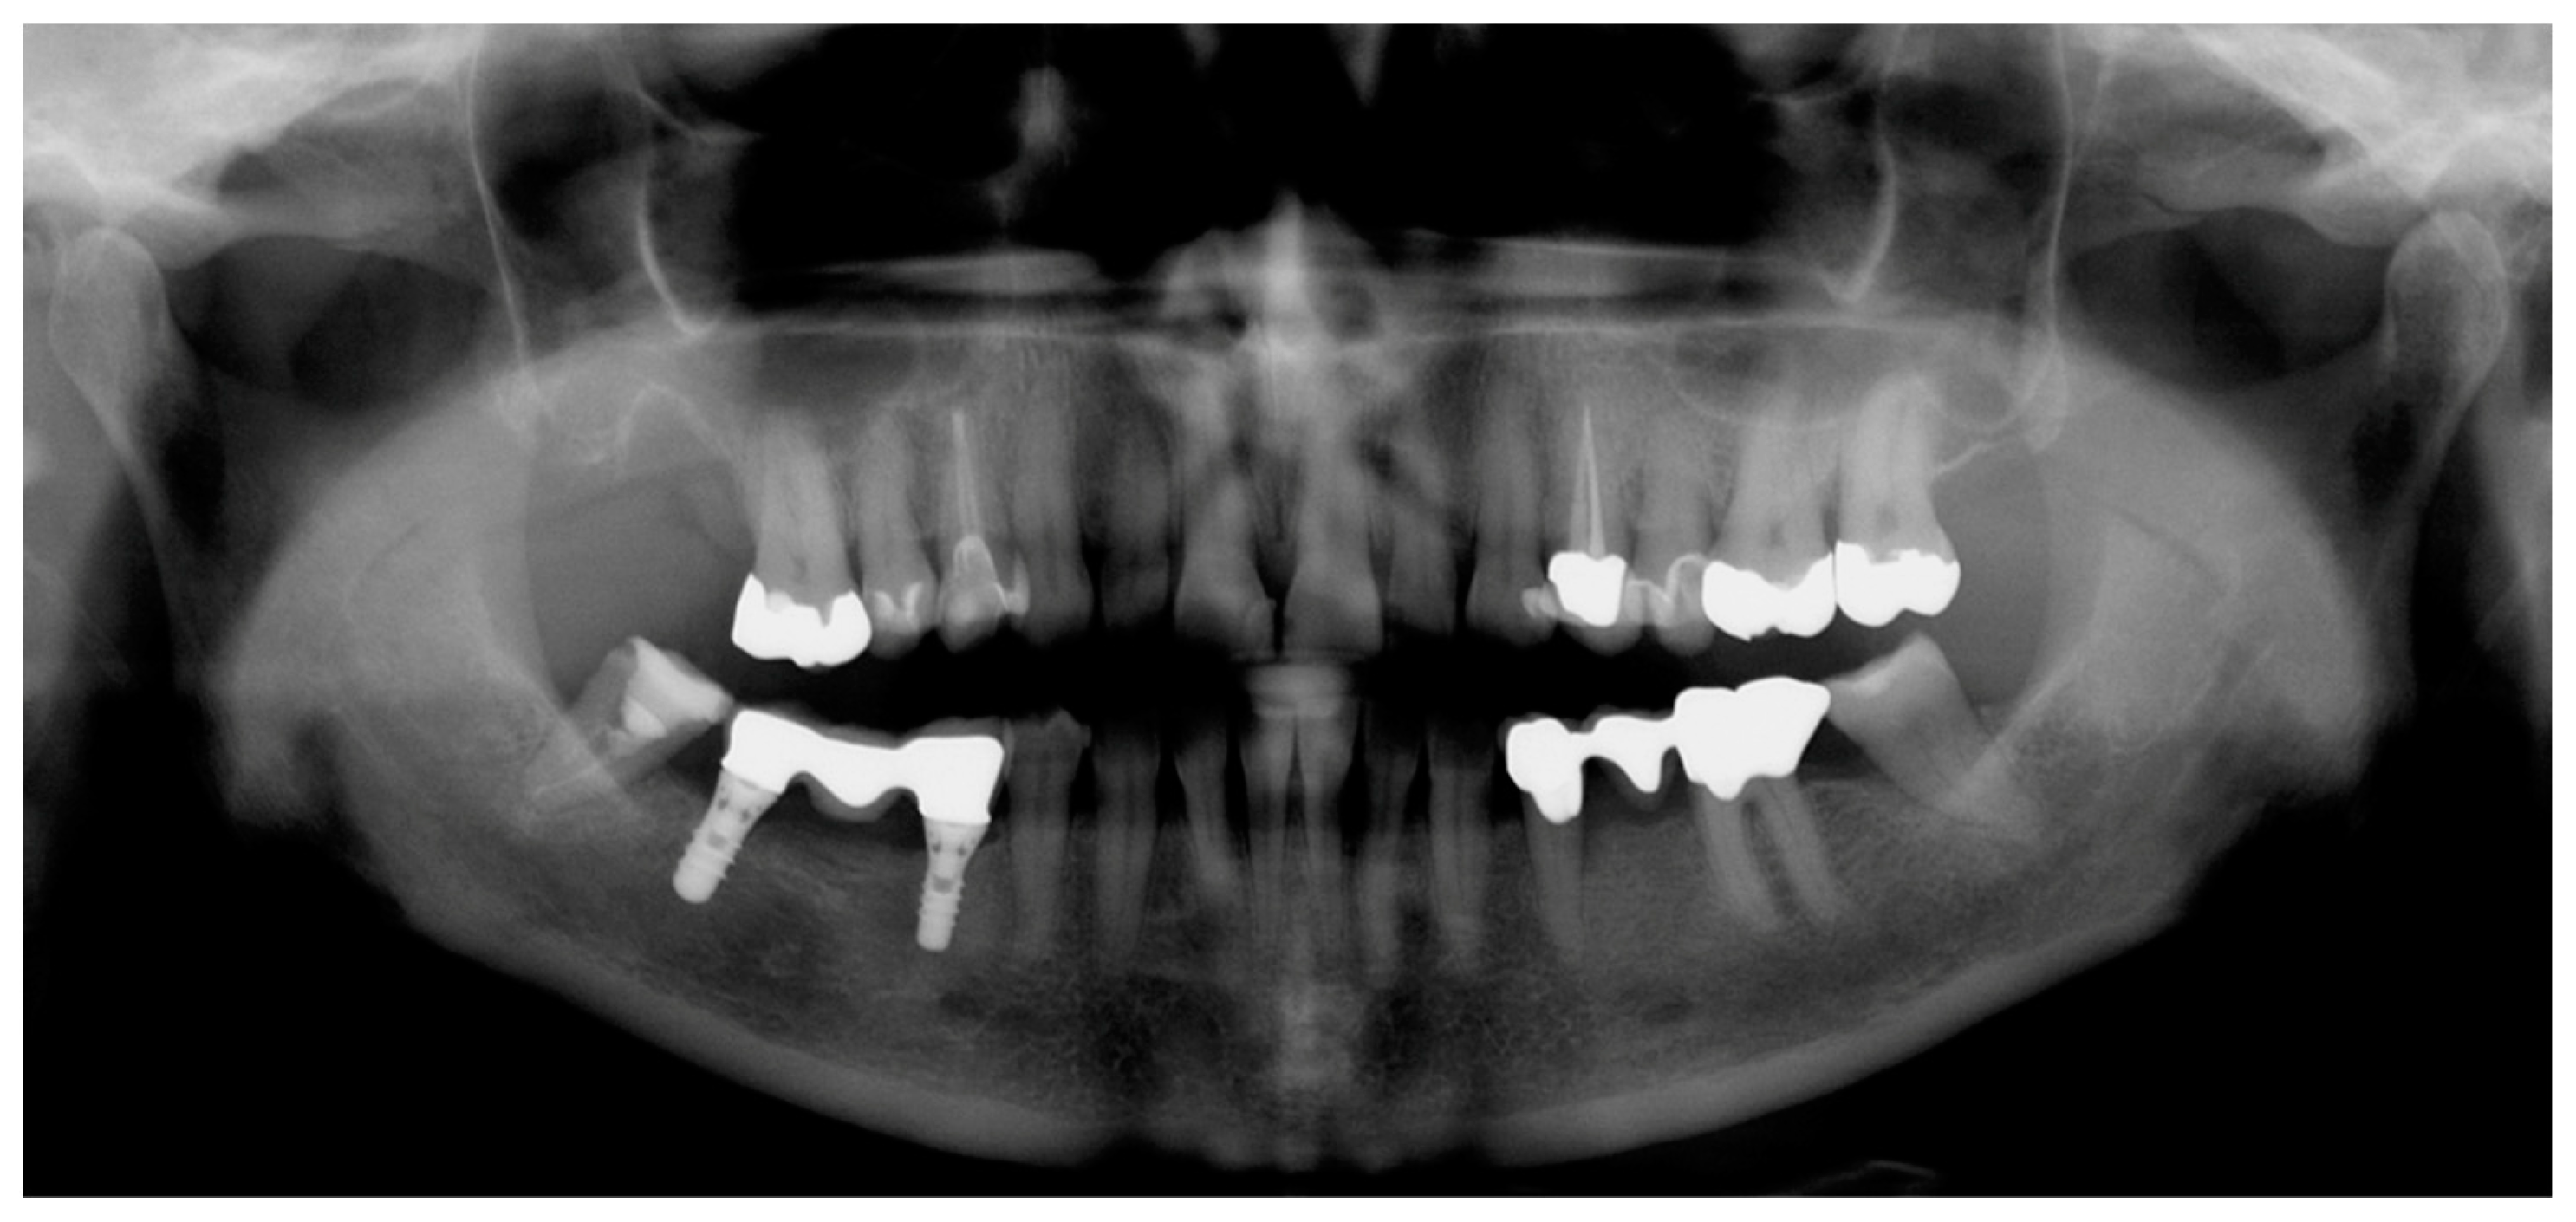

2.2. Radiographic Methods